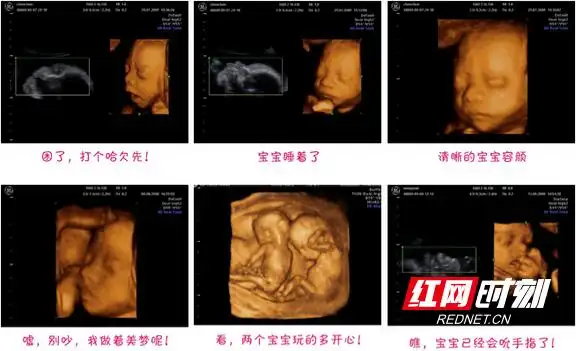

产科b超知多少